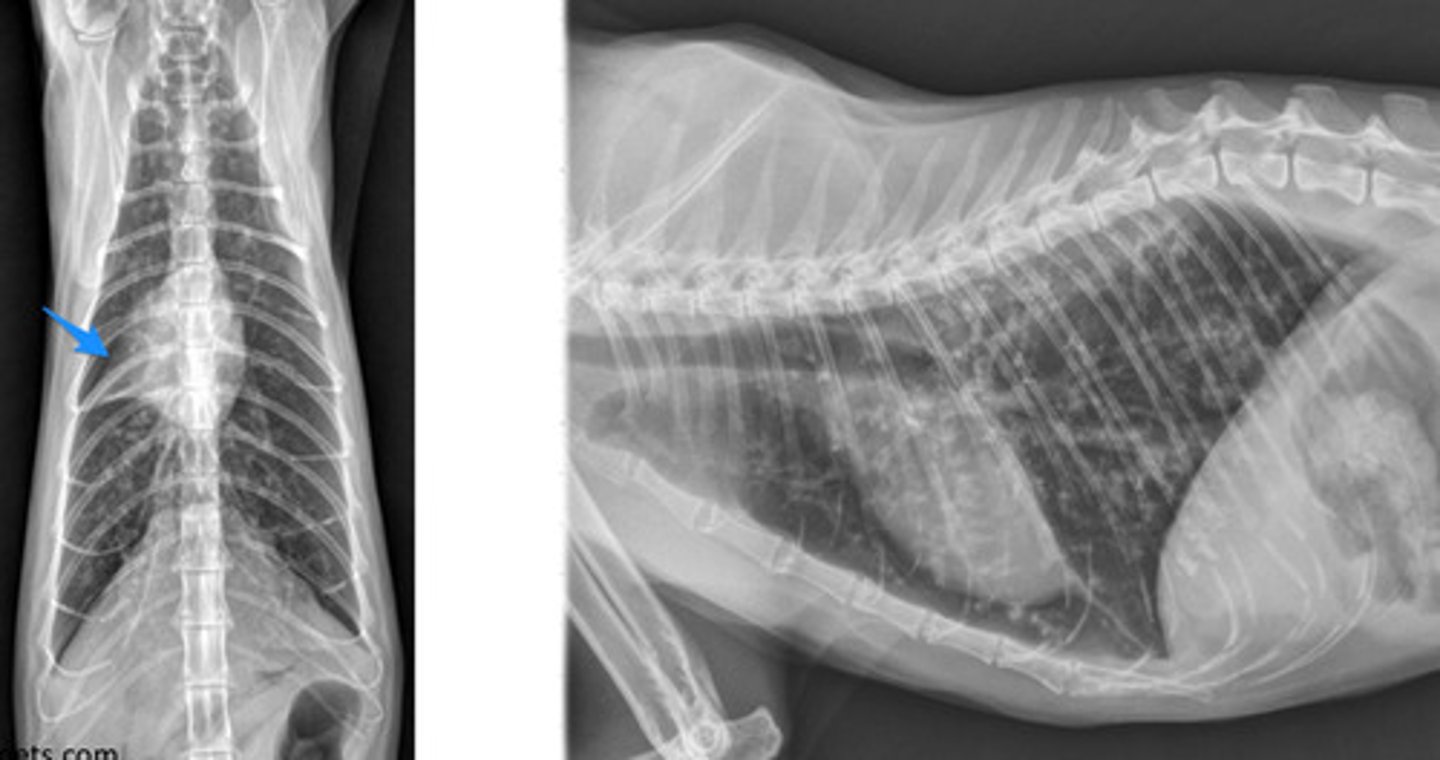

What body cavity do you take an x-ray of when the patient is at peak inspiration?

thoracic.

Where do you measure for thoracic radiographs?

caudal end of the scapula to the diaphragm/last rib.